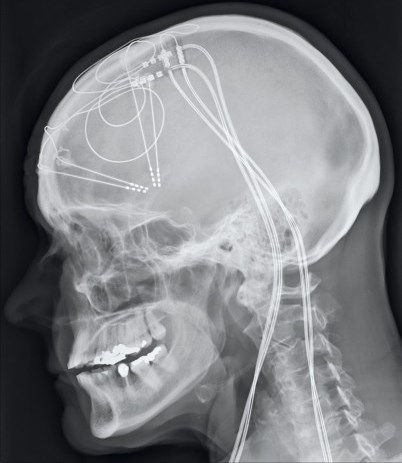

DBS for OCD at UCH

Deep brain stimulation (DBS) is well-established as a treatment for Parkinson's disease and other movement disorders. But this July, the hospital used DBS for the first time to treat a patient with severe obsessive-compulsive disorder (OCD). >>More